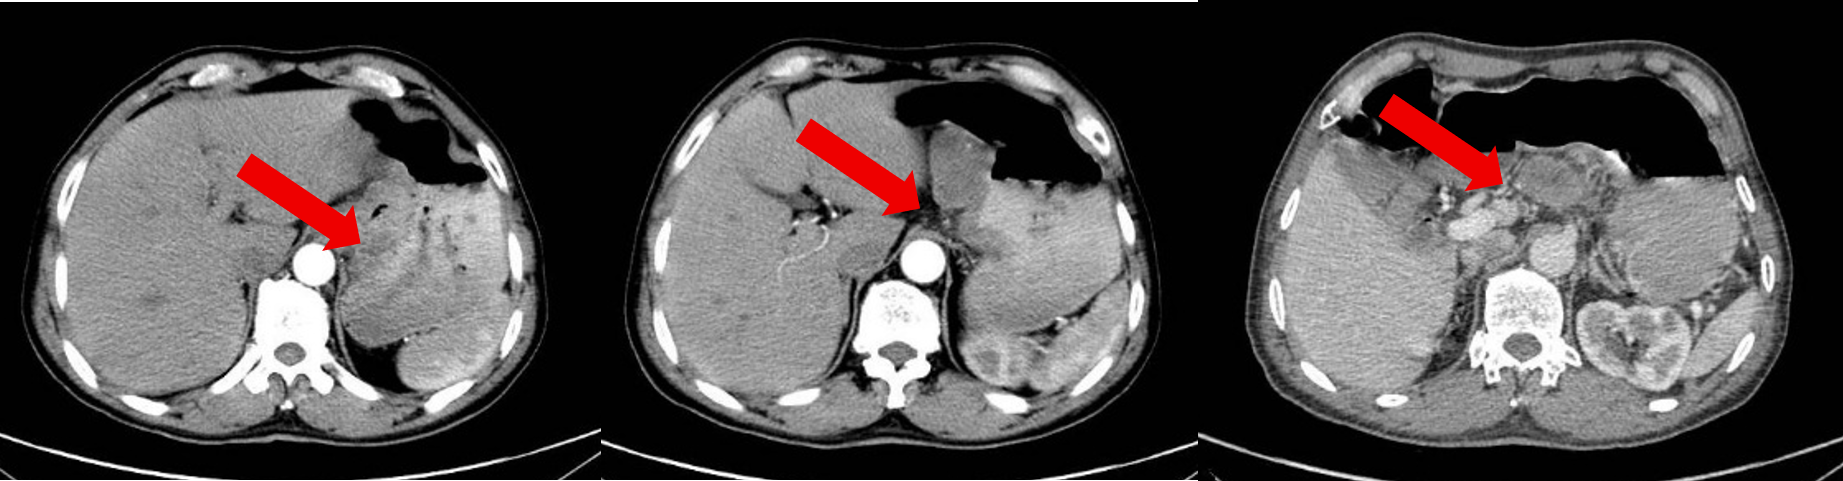

治疗2周期后患者于2024-10-20复查腹部CT:胃底、胃体小弯侧胃壁不均增厚,与邻近贲门分界不清,较前减轻,病灶较厚处约1.3cm。贲门左、胃小弯及肝胃间隙数个增大淋巴结,多系转移,多数较前缩小,大者大小约3.0×1.7cm。

治疗4周期后患者于2024-12-27复查腹部CT:胃底、胃体小弯侧胃壁不均增厚,与邻近贲门分界不清,较前大致类似,病灶较厚处约1.3cm。贲门左、胃小弯及肝胃间隙数个增大淋巴结,多系转移,多数较前缩小,大者大小约2.6×1.6cm。